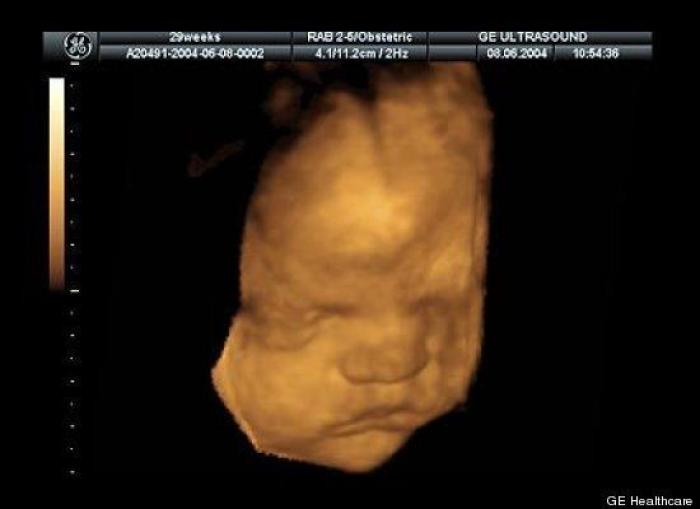

En esta galería puedes ver en fotos como es el desarrollo de un feto de semana en semana:

Desarrollo del feto, en fotos